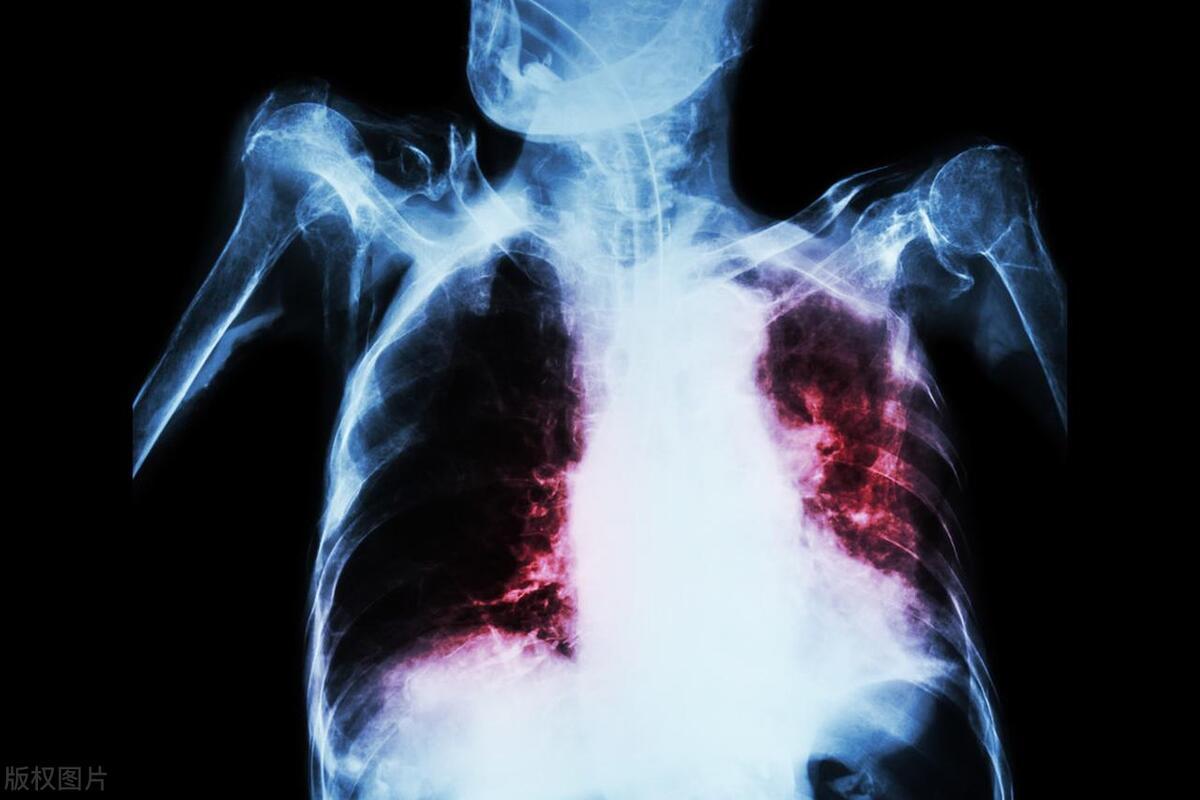

老楊此前在造紙廠主要擔任鍋爐電工,因爲平常工作接觸了大量的粉塵,所以老楊曾有氯化氫中毒史。此外,老楊還患上了間質性肺病,長期處於慢性缺氧狀態,他因此常年都臥病在牀。

3年前,老楊開始出現呼吸困難的情況。今年年初,老楊的症狀加重,還出現了呼吸衰竭。症狀加重後,老楊在深圳市人民醫院住院接受治療,直到好轉纔出院。然而2個月前,老楊的症狀復發,他因此又重新入住深圳市人民醫院接受治療。

老楊的肺移植手術事件讓醫療公平話題再次進入公衆視野,這件事裏同樣值得關注的其實還有肺健康問題。

中國人的肺都怎麼了?

很多人不知道,中國人的肺還真是一個大問題。2022年國家癌症中心數據顯示,我國每年的肺癌新發及死亡人數都是我國惡行腫瘤之首,堪稱癌症的“頭號殺手”。所以,不想讓肺出問題,預防肺癌,這幾件事一定要小心了。